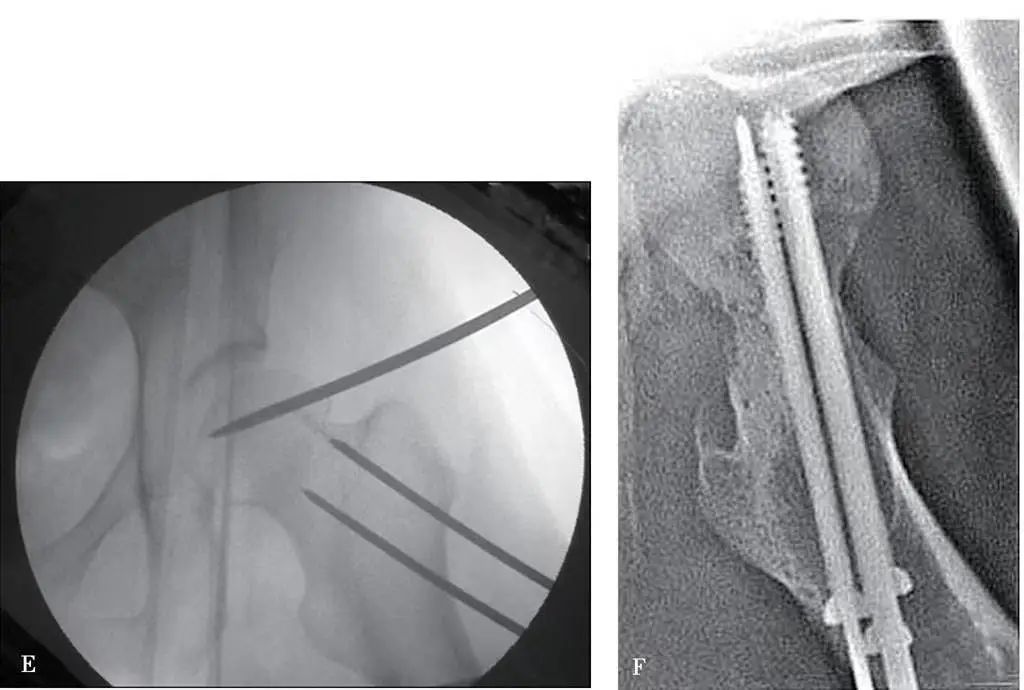

Костную циркулярную иглу диаметром 3,0–3,5 мм вводят вертикально через кожу на 1–2 см ниже места соединения паховой связки и бедренной артерии к передней части головки бедренной кости, после чего иглу поворачивают глубже к центру. головки бедренной кости под контролем аппарата С-дуги (рис. 1В).

Для усиления рвущей силы можно ввести вторую костную циркулярную иглу на 4-5 мм параллельно этой игле, оставив конец иглы вне кожи.

Через большой вертел чрескожно просверливают две костные циркулярные иглы диаметром 3,5 мм в соответствии с углом шейной ножки и углом наклона кпереди, достигая дистального конца перелома шейки бедренной кости (через перелом не проходят) и оставляя конец иглы вне кожи.

Оператор держит два набора хвостов игл обеими руками и регулирует секции перелома головы и шеи, чтобы они совпадали друг с другом при сотрудничестве с ассистентом (рис. 1C-E).

После удовлетворительного выравнивания костный круглый штифт, вставленный в большой вертел, ввинчивается в головку бедренной кости для временной фиксации, а затем в головку бедренной кости вставляют несколько полых винтов (рис. 1F).

Рис. 1. Перелом шейки бедренной кости, вправленный с помощью чрескожной иглы.